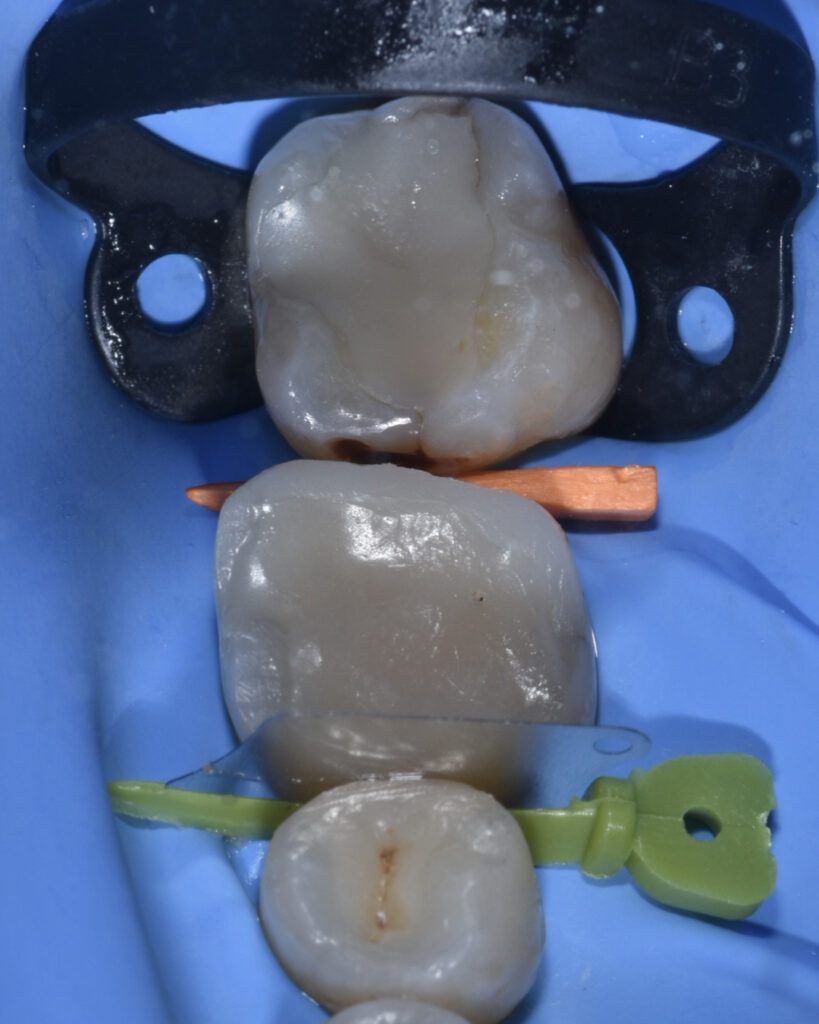

Endodontic treatment was performed using nickel–titanium rotary instrumentation, with irrigation protocols including sodium hypochlorite and 17% EDTA, both sonically activated.

The root canal system was obturated using a single-cone cold technique with a bioceramic sealer.